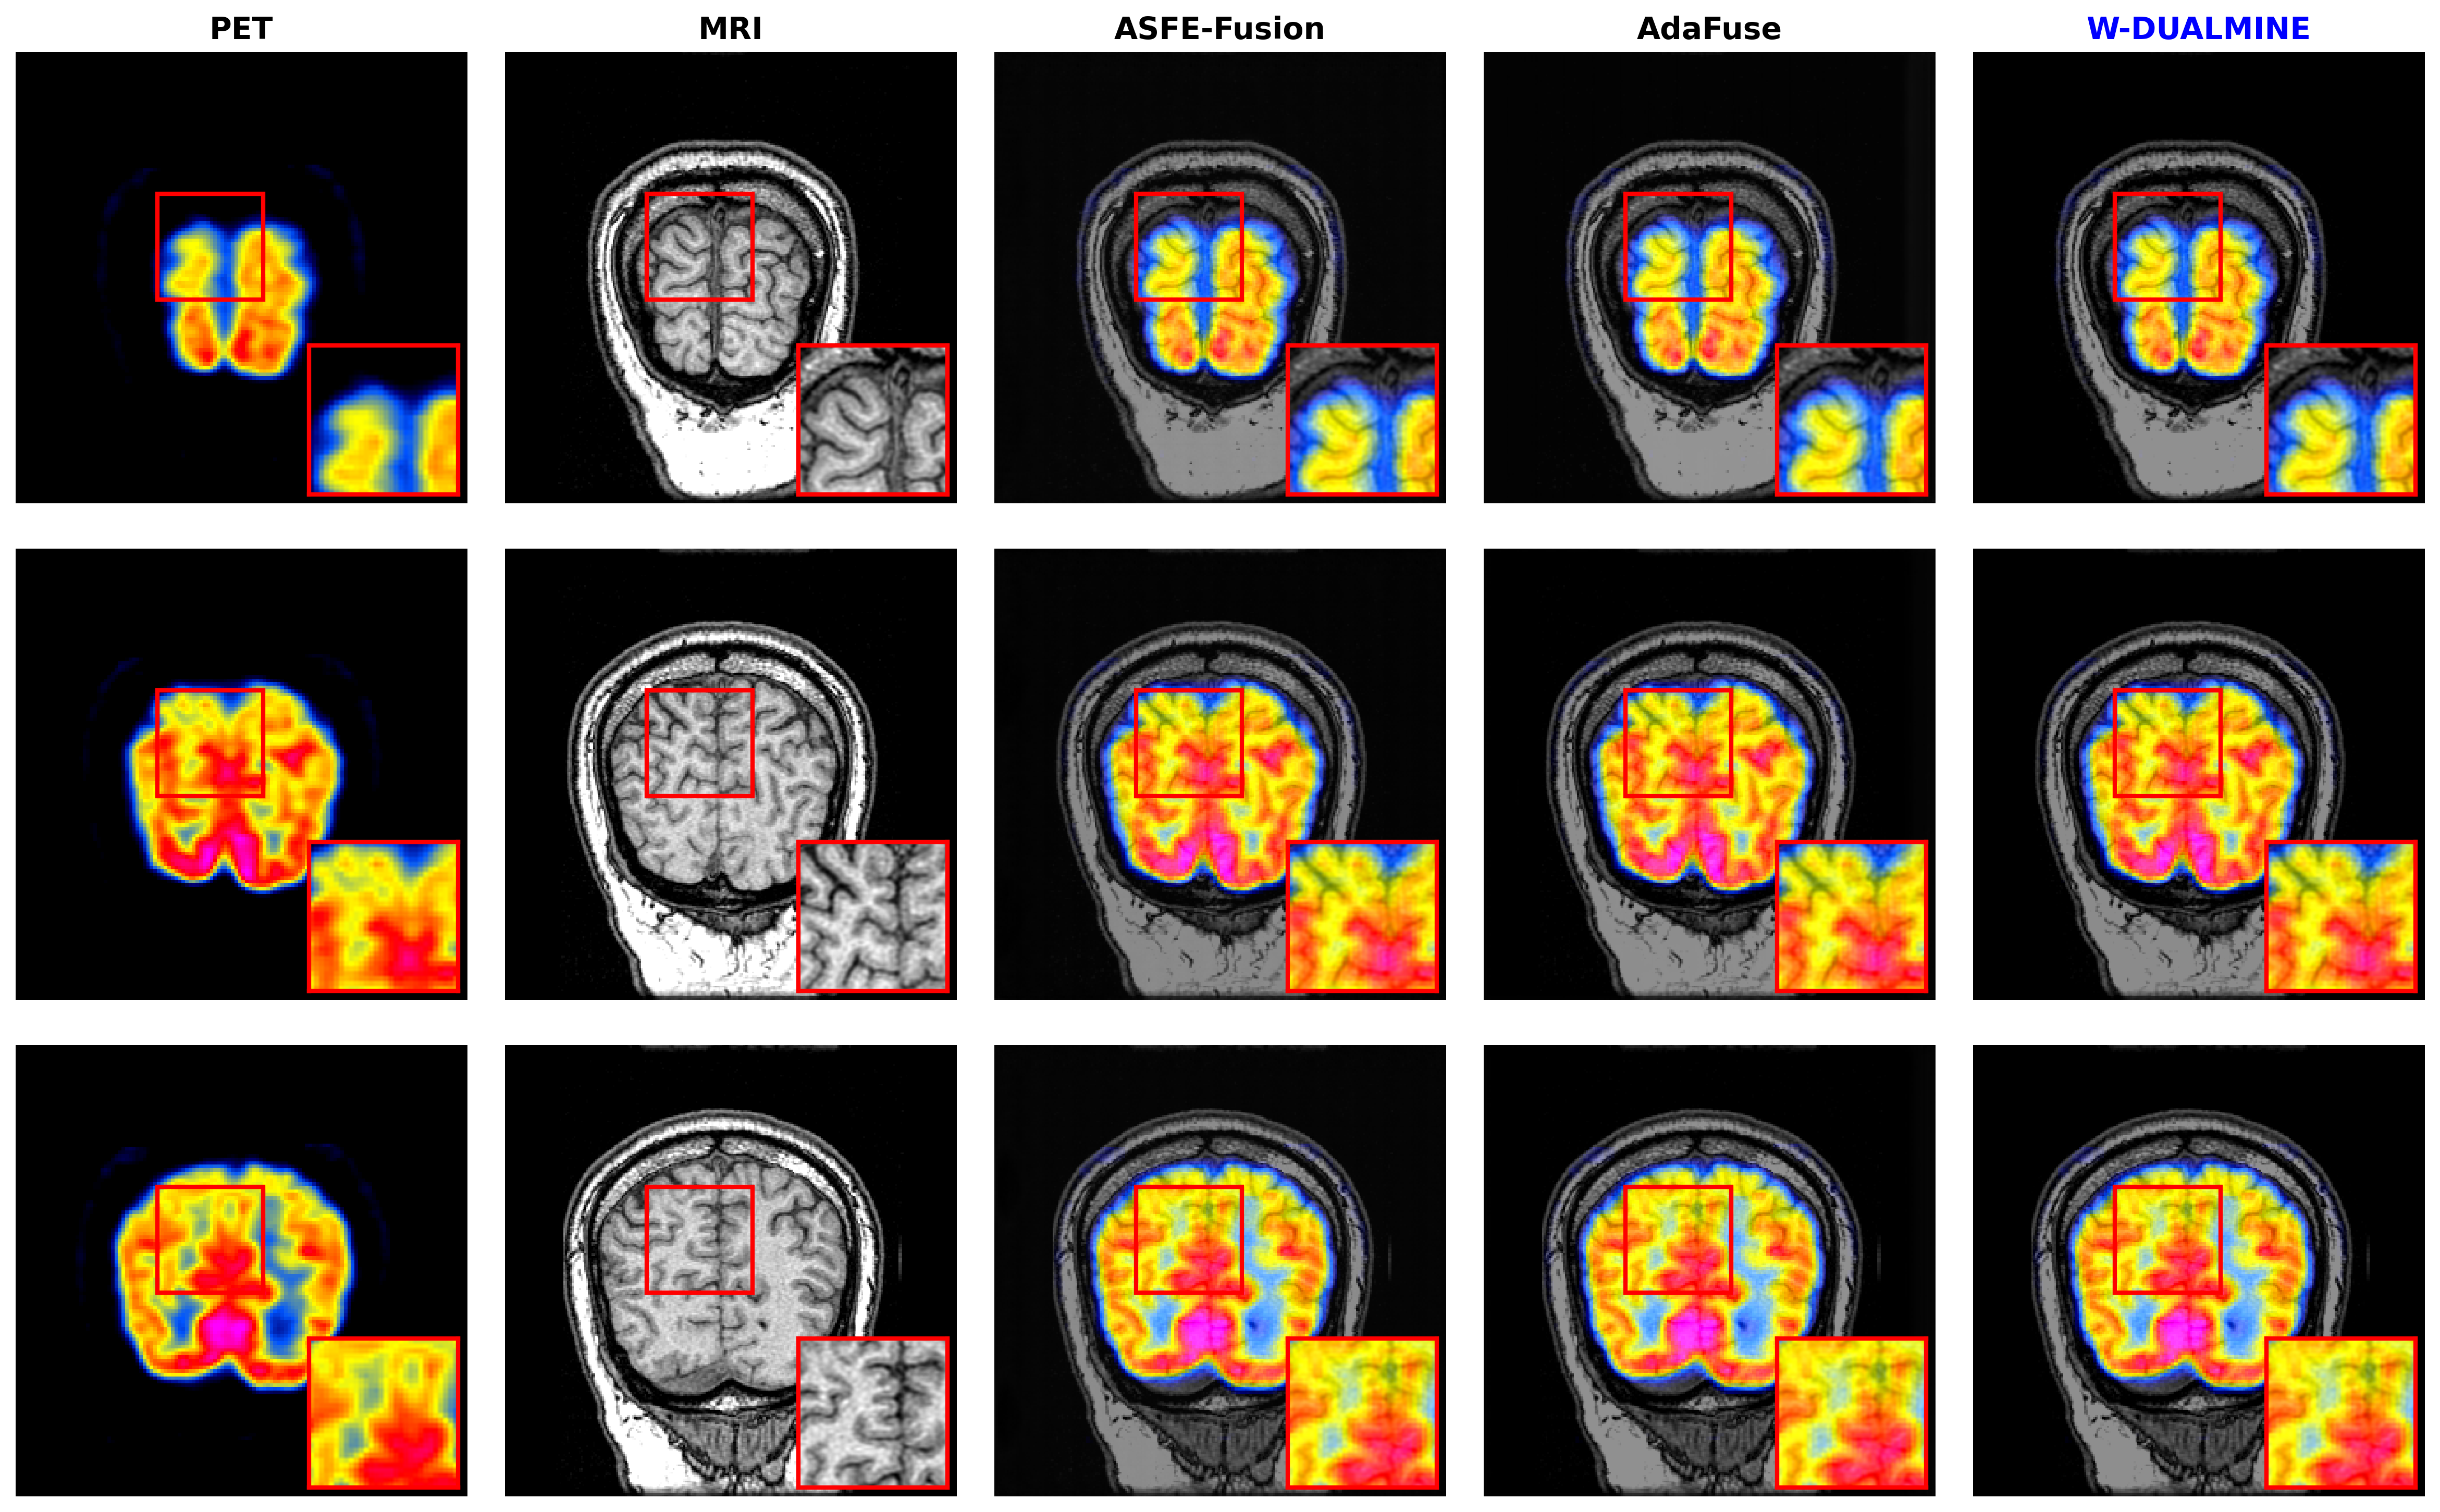

5.3.2 Results on PET–MRI Dataset

The PET–MRI dataset requires fusing low-resolution metabolic color information with high-resolution anatomical structures. Results are shown in Table 2.

Analysis: In this task, W-DUALMINE demonstrates a substantial advantage in Mutual Information (4.30684.3068 vs. 3.62213.6221 for ASFE), indicating superior transfer of functional metabolic cues. The FMI score (0.50640.5064) is notably higher than competitors, proving that the Wavelet Frequency Expert successfully isolates and preserves the high-frequency MRI details without being washed out by the PET signal. While ASFE-Fusion shows a marginally higher CC (0.86890.8689 vs 0.86860.8686), the difference is statistically negligible given the standard deviation (±0.023\pm 0.023), whereas this method’s gain in PSNR and FMI is distinct.

Refer to caption

Figure 4: Qualitative comparison on the PET–MRI fusion task. From left to right: PET image, MRI image, ASFE-Fusion, AdaFuse, and W-DUALMINE. Highlighted regions demonstrate superior preservation of functional activity without color diffusion.

5.3.3 Results on SPECT–MRI Dataset

The SPECT–MRI dataset represents a challenging scenario with significant resolution disparity between modalities. Results are summarized in Table 3.

Analysis: W-DUALMINE achieves robust performance on SPECT–MRI, recording the best MI (4.00164.0016), CC (0.91160.9116), and PSNR (64.908464.9084). The improvement in PSNR is particularly critical here, as SPECT images often contain scattering noise. The Reliability Maps in the encoder effectively identify and suppress these unreliable regions before fusion, leading to a cleaner fused image compared to ASFE-Fusion, which tends to amplify noise (evidenced by higher Entropy but lower PSNR and FMI).

Figure 5: Qualitative comparison on the SPECT–MRI fusion task. From left to right: SPECT image, MRI image, ASFE-Fusion, AdaFuse, and W-DUALMINE. The proposed method maintains low-contrast functional regions while preserving anatomical structure.

As shown in Figs. 35, W-DUALMINE produces visually superior fusion results across all modalities. The proposed method achieves better structural clarity and functional consistency than ASFE-Fusion and AdaFuse, particularly in highlighted regions.